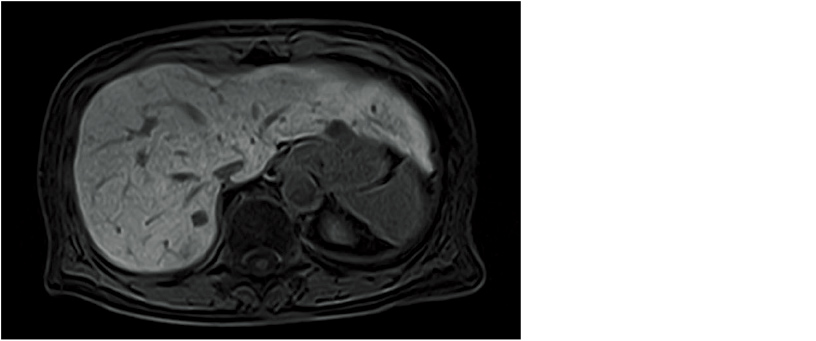

The use of TIGRE enables dynamic imaging in organs such as the liver. The large fat component in the abdomen and breast regions require high-precision fat suppression. We have realized uniform fat suppression effects and dynamic imaging in the abdomen and breast through combined use of high uniformity of the static magnetic field and H-Sinc which corrects for RF non-uniformity.

Abdominal dynamic image (TIGRE)

This function can map the distribution of T2* values to improve the visibility of iron deposition in liver tissue. A special sequence based on the GRE method (ADAGE) is available to acquire MultiEcho images used to automatically calculate T2* values. When analysis is conducted on the console, a color map of these T2* values is superimposed on a morphological image to create a T2* RelaxMap.

You can also create an R2 (Relaxation rate) map based on 1/T2* values. The relative color display of an area with shortened T2* values can be used as a quantitative evaluation of iron deposits.